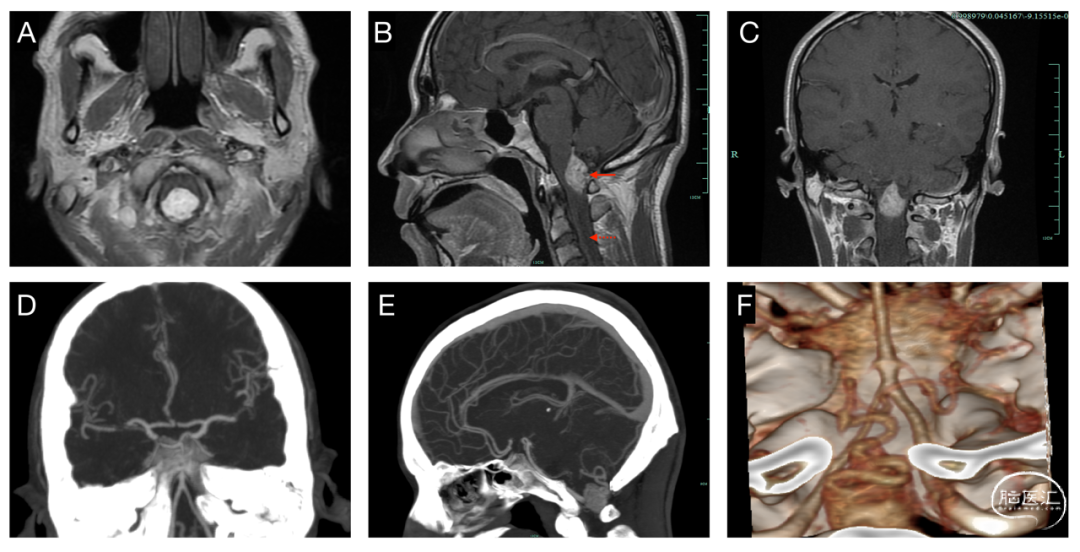

镜下见毛细血管瘤样增生,可见散在间质细胞,部分细胞核大,核分裂像少见 (图3 C)。免疫组化:Ki-67(2%+)、CD34(+)、CD68(-)、GFAP(-)、EMA(-)。病理诊断:血管母细胞瘤。

术后第1天,患者原手指麻木症状完全消失,伴有轻度本体感觉障碍,合并轻度呃逆,四肢肌力、痛觉正常,无明显吞咽功能障碍。术后当天CT提示病变完全切除,术区无出血(图3 A)。术后颅脑MR增强提示肿瘤全切。术后1周患者本体感觉障碍消失,呃逆症状消失,可以自行下床活动,无明显神经功能缺损。

图3. 术后影像资料及病理。(A)术后当天复查头颅CT,术区无明显出血,无明显脑肿胀;(B)术后第5天复查颅脑MR增强,提示肿瘤完全切除;(C)HE染色提示毛细血管瘤样增生,可见散在间质细胞,部分细胞核大,核分裂像少见(200 X)。